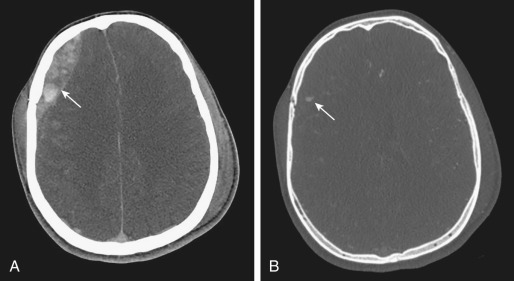

SDH